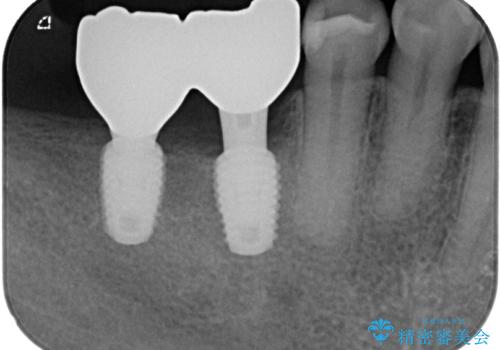

- 以前抜歯をして歯がないところにインプラント治療をしたいと来院された患者様です。

1年くらい前に他院で抜歯をしたそうです。

レントゲンで確認すると骨は十分にあるので通法通りインプラントによる補綴治療を行いました。